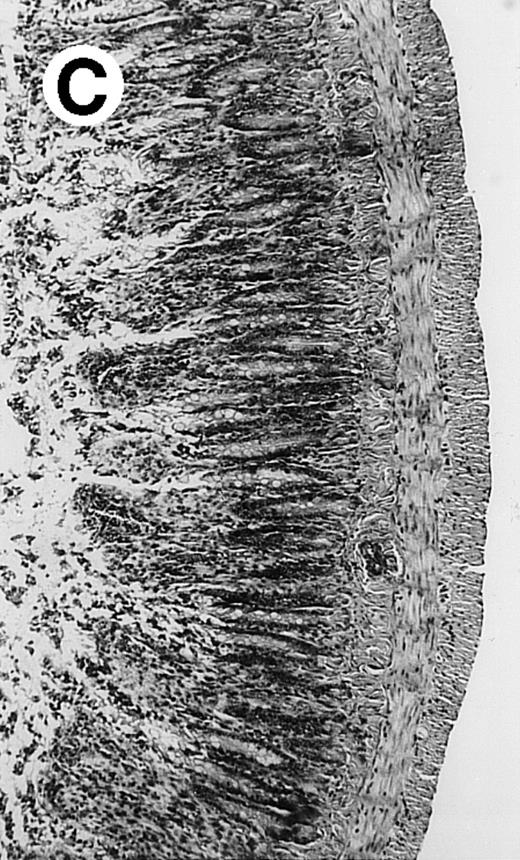

Pathologic findings in the small and large intestine were strikingly different depending on the treatment group. Figure 2A shows a representative pathologic sample from an animal assigned to the control group. Marked thinning of the bowel wall and extensive areas of epithelial cell sloughing was noted. Animals randomized to rhG-CSF treatment had minimal improvement in histologic findings with focal regions of preserved epithelium (Fig2B). Animals randomized to the rhIL-11 group showed substantial improvement with thickening of the epithelial layer and preservation of mucosal cell integrity (Fig 2C). Animals receiving both rhG-CSF and rhIL-11 had the most favorable histologic findings with normal mucosal thickness, minimal inflammatory changes, and preserved tissue architecture (Fig 2D). The composite analysis of the gastrointestinal pathology is provided in Table 1.

Histopathology of small intestinal mucosa cut in transection from an animal in each treatment group (study day 8). The upper panel (row 1) is a low power view (original magnification × 57); the lower panel (row 2) is a high power view (original magnification × 144). Note the diffuse thinning and necrosis of the mucosa with sloughing of intestinal epithelial cells in the control animal (A). There is progressive recovery of the thickness of the mucosa, reduction in inflammatory changes, and improved epithelial architecture with rhG-CSF (B), rhIL-11 (C), and combination therapy with rhG-CSF+IL-11 (D).